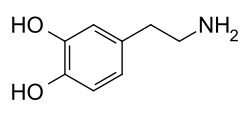

Evidence indicates that the mechanism of hyperpituitarism can originate from genetic disruption causing pituitary tumorigenesis, most pituitary adenomas are monoclonal, which in turn indicates their origin from an event in a single cell.[2] There are three hormones that are oversecreted resulting in the pituitary adenoma: prolactin, adrenocorticotropic hormone (ACTH), and growth hormone (GH).

Excess prolactin may result in a prolactinoma[7] Excess GH results in gigantism, the severity of gigantism depends on whether the epiphyseal plate is open.[8] The four most common types of hyperpituitarism are caused by 4 types of pituitary adenoma, as follows: prolactinoma, corticotropinoma (Cushing's disease), somatotropinoma (gigantism), and thyrotropinoma .[9]

Treatment (for hyperpituitarism) in the case of prolactinoma consists of long-term medical management. Dopamine agonists are strong suppressors of PRL secretion and establish normal gonadal function. It also inhibits tumor cell replication (in some cases causes tumor shrinkage)[13] Treatment for gigantism begins with establishing target goals for IGF-1, transsphenoidal surgery (somatostatin receptor ligands- preoperatively) and postoperative imaging assessment.[14] For Cushing's disease there is surgery to extract the tumor; after surgery, the gland may slowly start to work again, though not always.[15]